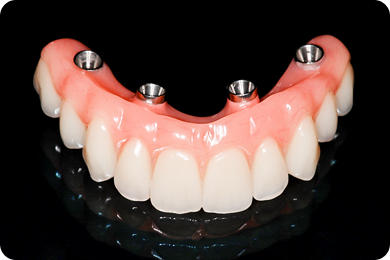

Зубы за 1 день за 5776р. в месяц

с пожизненной гарантией

По уникальной методике

БЕЗ отёков и надрезов

Установка

за 1 день